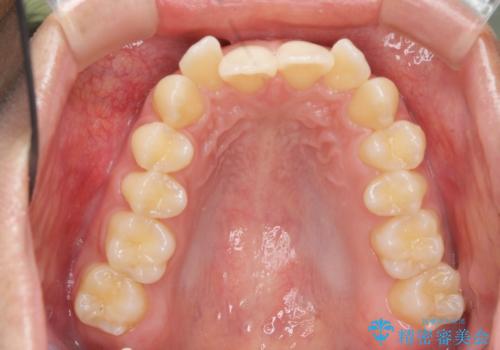

過蓋咬合・上顎前突・叢生を改善するマウスピース矯正

- 前歯のがたつき、不揃いさの改善を求めて来院されました。

・前歯の深い噛み合わせ (過蓋咬合)

・上顎前突(Angle Class2)

・叢生(がたつき)